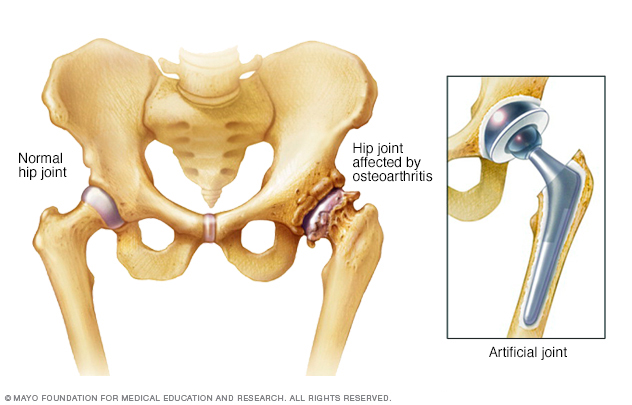

இடுப்பு எலும்பில் ஏற்படும்பாதிப்பால் இன் நிலை ஏற்படுகின்றது.தொடர்ச்சியான இடுப்புவலியாக இல்லாமல் இடையிடையே இடுப்புவலி வந்து செல்லும்.ஆண்களில் விதையில் வலி ஏற்படும்.முக்கியமாக காலைவேளைகளில் மூட்டுக்களை அசைப்பது இருத்தல் எழும்புதல் கடினமாக இருக்கும்.

ஜாயின்ட் ரீபிளேஸ்மன்ற் surgery (joint replacement surgery)-இதன்மூலம் பாதிக்கப்பட்ட மூட்டு முழுவதுமாக அகற்றப்பட்டு செயற்கைமூட்டு பொருத்தப்படும் இதன்மூலம் அடுத்த 10-15 வருடங்களுக்கு எந்த வலியும் இல்லாமல் வாழமுடியும்.